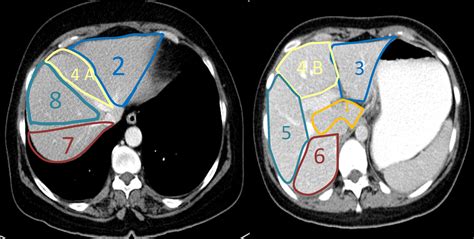

• Pre-surgical planning: Helping surgeons map out the liver's blood vessels and structural anatomy before procedures.

When a radiologist reviews the liver on CT, they look for specific "attentuation" patterns. Healthy liver tissue has a uniform appearance. Deviations from this indicate pathology. For example, fatty liver disease (steatosis) often presents as a darker, low-density appearance compared to the surrounding spleen or vessels. Conversely, iron overload (hemochromatosis) causes the liver to appear significantly brighter (more dense) on a scan.